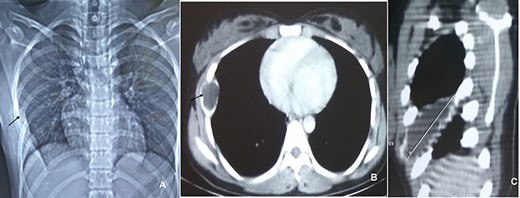

A 15-year-old girl present with lump in right chest with gradually progressing discomfort of 6-month duration. The discomfort was constant with intermittent exacerbation. She had no history of trauma or prior chest surgery, and her past medical history was unremarkable. Her physical examination revealed a palpable mildly tender mass on sixth rib on anterolateral wall of the right chest. Her routine laboratory test results, including complete blood count, erythrocyte sedimentation rate, renal function test and liver function tests, were all within normal range. Chest radiograph performed showed destruction of right sixth rib (Fig. 1A). CT chest revealed 36 × 30 × 80 mm well-defined large uniloculated cystic lesion of the sixth rib involving anterolateral part and abutting the costochondral junction (Figs 1B and C). She underwent surgery after all diagnostic investigation was completed.

CXR (A, arrow) showing mass lesion in sixth rib. CT chest axial (B, arrow) and saggital (C) showing uniloculated bone cyst.